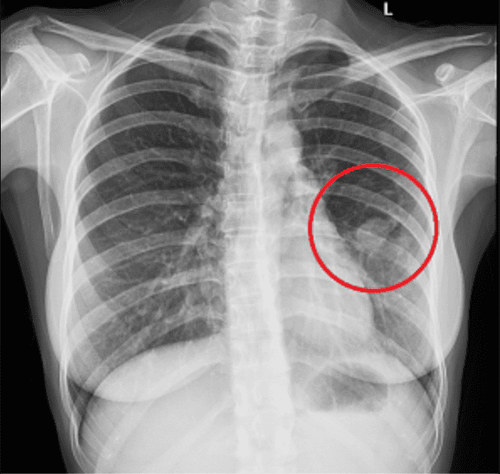

Chụp cắt lớp vi tính mang đến hình ảnh có độ phân giải cao, tạo nên giá trị cốt lõi để chẩn đoán chính xác về tình trạng bệnh phổi tắc nghẽn mạch của các bệnh nhân.

Phương pháp này giúp xác định được vị trí cùng với độ rộng, mức độ nặng nhẹ của khí phế thũng khi mà xquang tim phổi và những chỉ số trên đo chức năng hô hấp vẫn cho kết quả bình thường.

Ngoài ra, kỹ thuật này cũng thường được sử dụng khi cần phải phát hiện ra sự giãn phế quản kết hợp cùng với bệnh phổi tắc nghẽn mạn tính.

Những hình ảnh liên quan đến tổn thương phế quản hoặc tiểu phế quản: cho thấy dày thành phế quản trông giống như hình đường ray hay hình nhẫn, hoặc vòng tròn lòng sáng.

Hình ảnh khí phế quản thũng: chụp cắt lớp vi tính có thể giúp chúng ta nhìn rõ được những vùng mô giảm tỷ trọng và giảm những mạch máu phổi, thậm chí là thấy rõ những bóng khí thũng,...

● Sử dụng chụp cắt lớp vi tính hoặc chụp X Quang phổi để thu nhận những hình ảnh liên quan đến phổi và các hình ảnh khí thũng phổi.